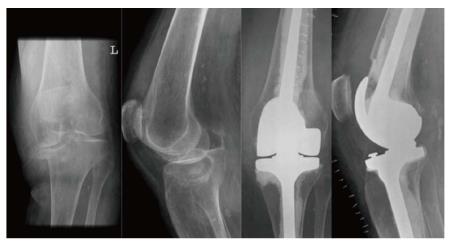

Radiographic Predictors of Conversion to Total Knee Arthroplasty After Tibial Plateau Fracture Surgery: Results in a Large Multicenter Cohort